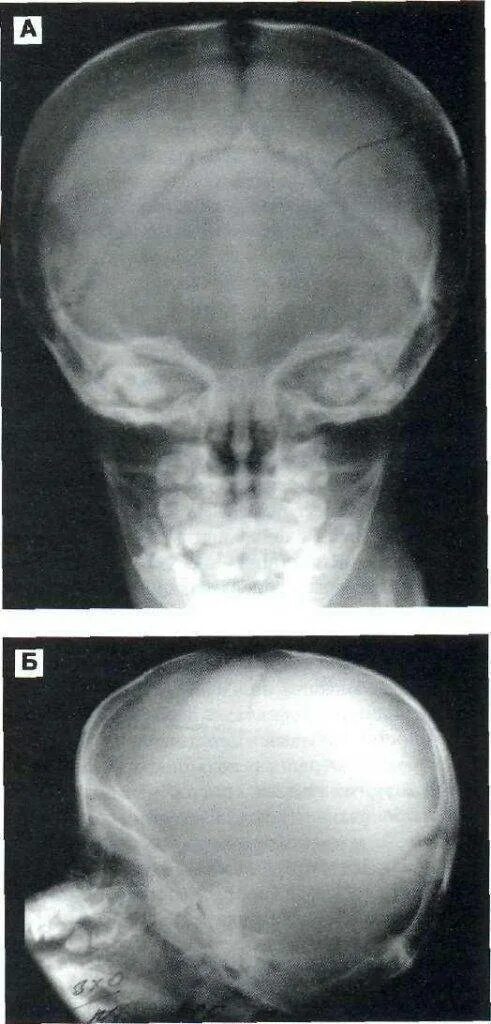

Оскольчатый перелом черепа